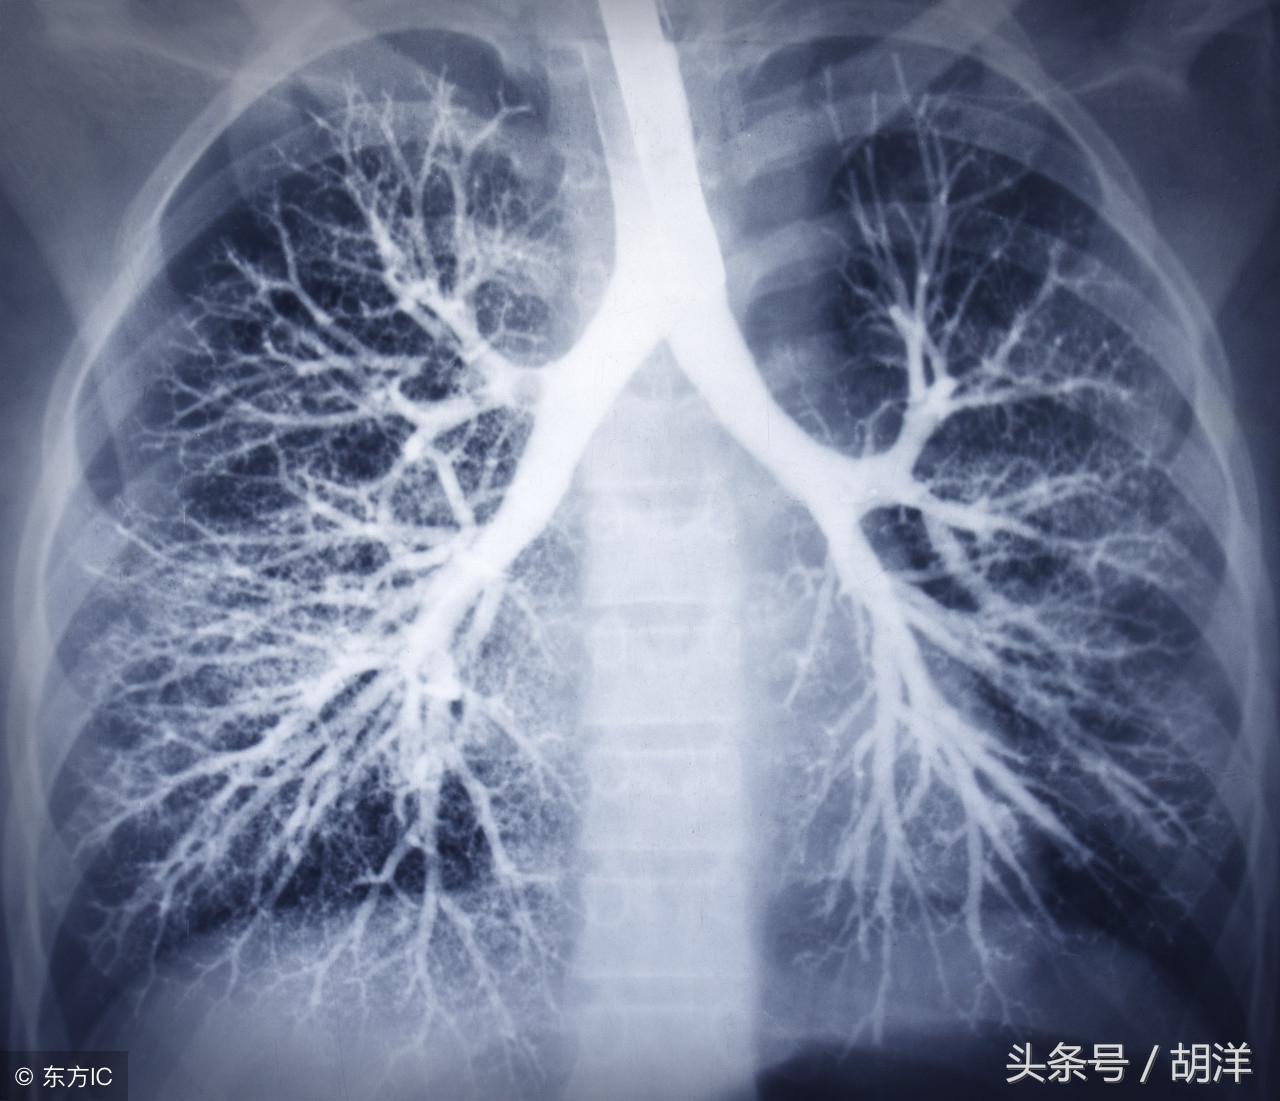

咳血又称咯血,是呼吸科一个比较严重的症状,由于其可能提示肺部肿瘤等严重疾病而受到重视,但事实上在引起咯血的病因中,肺部恶性肿瘤所占的比例并不是很大,但很多人因咯血而焦虑异常,特别是咯血久治不愈情况下,更加令人无法正常的生活和学习,那么哪些疾病可能导致反复发作痰中带血或者咳出满口鲜血呢?

支气管扩张

支气管扩张是一种支气管管壁结构破坏性疾病,正常情况下,支气管是一个带有弹性,拥有一定管径的能够维持正常呼吸通气的结构,当管壁结构受到破坏时,气管会受到被动的牵拉而扩张,管壁的血管由于弹性较小,容易被撕扯呈血管瘤改变,一旦胸腔内血流压力增大可能冲破血管瘤变薄的管壁而导致大咯血,少量渗血时则呈现为痰中带血。

肺结核

肺结核是一种肺部传染性疾病,是由于结核菌在肺部生长并破坏肺部结构导致的,对于肺部的损害很大,寄生的肺组织局部甚至会完全毁损形成干酪样坏死物排出体外,这样的破坏难免侵蚀血管导致出血,也是大咯血的原因之一。

肺癌

肺癌也是较为常见的导致咯血的原因,恶性肿瘤细胞对于肺组织的侵蚀是其他疾病无法比拟的,几乎可以侵犯肺部正常组织中的所有结构,包括血管,另外,肺癌癌肿由于生长过快,其表面的细胞可能会因为得不到充足的血液供应而坏死,这样的坏死很容易产生渗血,是引起痰中带血的常见原因。

肺炎

肺炎引起咯血的原因和肺结核类似,都是由于肺部细菌感染后破坏正常肺结构引起渗血以及血管破裂所致。